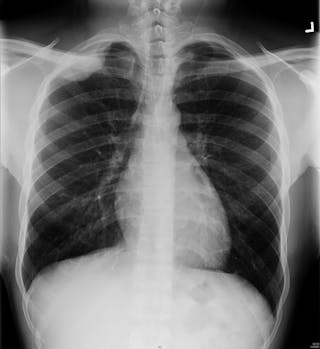

Ein Röntgenbild zeigt Grautöne, die zeigen, wie viel des Röntgenstrahls durch den Körper gelangt. Wenn der Teil sehr dicht ist (wie Knochen), erscheint er weiß, wenn er weniger dicht ist (wie die Lunge), erscheint er in einem dunkleren Grauton.

Röntgenstrahlen sind wie Lichtstrahlen, aber der Unterschied ist, dass sie mehr Material durchdringen können. Haut und Fett blockieren nicht viel von der Energie des Röntgenstrahls. Muskeln blockieren mehr, aber noch mehr Energie wird von Knochen blockiert, weshalb man Knochen auf Röntgenbildern so deutlich sehen kann.